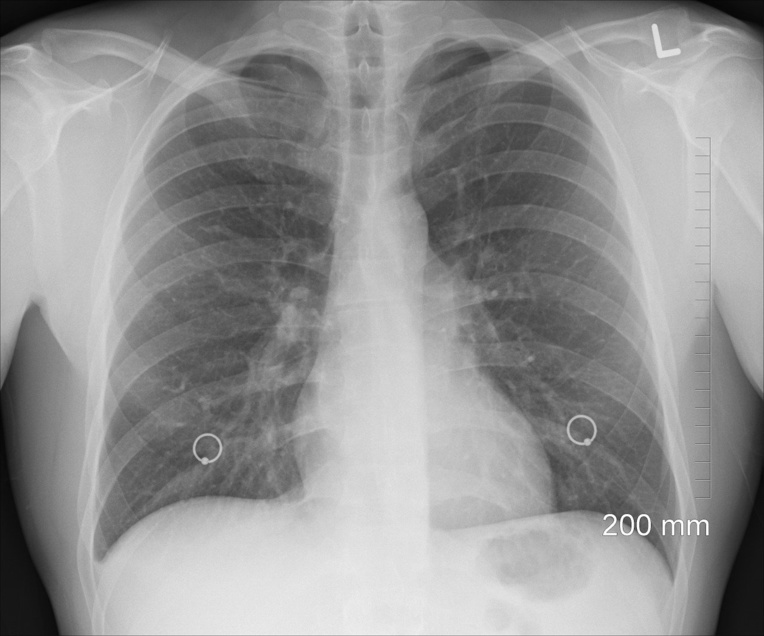

L'outil a été élaboré en lui transmettant des milliers de radios de personnes ayant contracté la maladie Covid-19 et de personnes saines, afin qu'il apprenne à distinguer les marqueurs de la maladie dans les poumons.